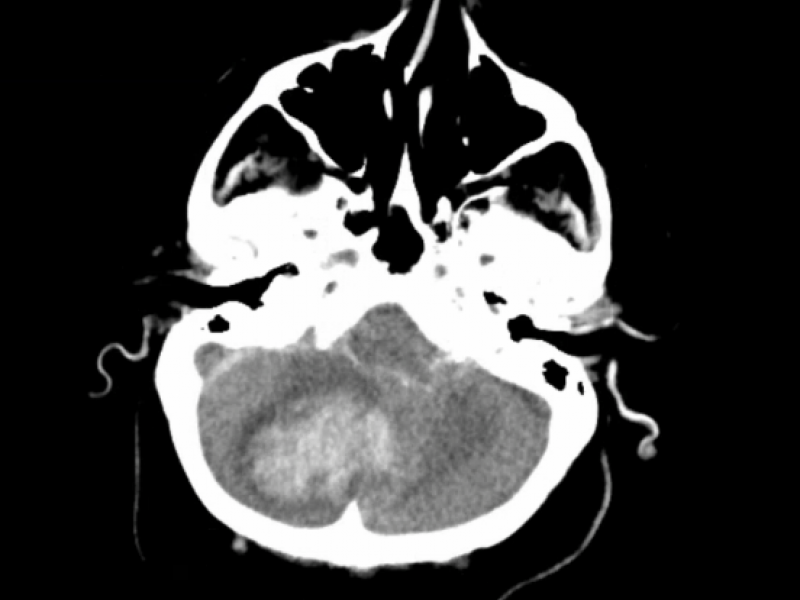

What's the diagnosis?  By Dr. Loran Hatch

December 26 2018

An 81 yo female presents with acute onset AMS approximately

EM Daily